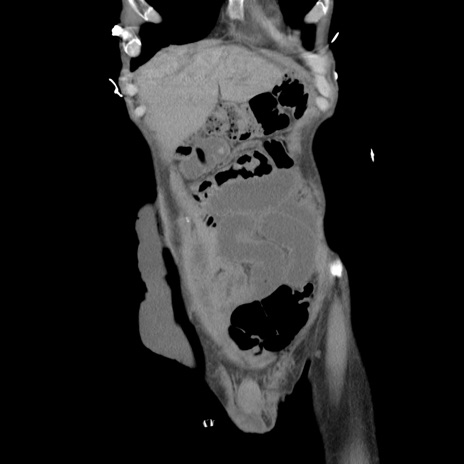

症例11(冠状断像)

【症例】 60歳代男性

【主訴】 下腹部痛

【現病歴】 本日夜中より下腹部痛の症状認め、受診。

【既往歴】 膀胱癌(膀胱全摘+尿管皮膚瘻術) 、胃癌術後

【身体所見】 BT 35.3℃、PR 58/min、BP 136/98mHg、腹部平坦、軟、腸蠕動音±、ストマ留置あり、左上腹部~正中部に圧痛あり、反跳痛なし。

【データ】WBC 5100、CRP0.01